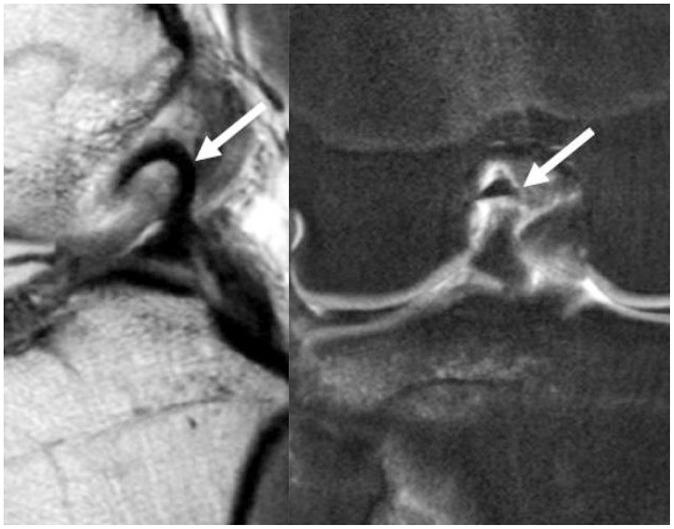

To accurately interpret knee MRI, it is important not only to know the basic meniscal anatomy but also to distinguish it from that under pathological conditions. Thus, it would be helpful to know the normal meniscus variants (false positives) that could be mistaken for meniscal tears, and tears that could easily be missed and incorrectly diagnosed as normal (false negatives). False positives include synovial recesses, meniscal flounce, the relationship between the popliteus tendon and lateral meniscus, transverse ligament, the anterior root of the meniscus, and meniscofemoral ligament. False negatives include focal radial tears, flap tears, posterior root tears, meniscocapsular separation, and discoid meniscal tears. In this pictorial essay, we reviewed the imaging data obtained in the aforementioned cases.